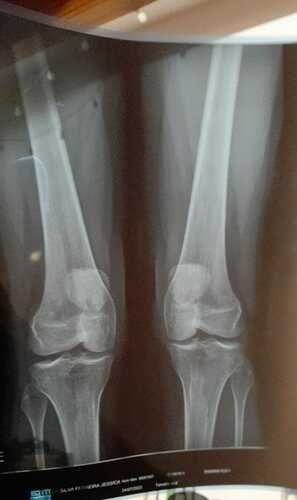

Meu nome é Jessica e tenho 24 anos, desde pequena sinto muitas dores nas pernas e os médicos diziam que era dor de crescimento, e até reumatismo e a dor foi só aumentando até que a rotula do joelho começou a sair do lugar, fiz alguns exames e descubri que tenho displasia rotuliana tipo c e condromalacia grau 4( não há mais cartilagem nos 2 joelhos) e com o passar dos anos foi piorando e agravando também a tibia.

hoje não consigo mais andar bem, nem fazer as coisas básicas do dia a dia, pela dor e por que a rotula sempre sai do lugar. Por isso criei a vakinha virtual para arecadar 50.000 mil reais para fazer as cirurgias particular, pois ja estou na fila do sus a 4 anos apenas para primeira consulta. Quero muito fazer a cirurgia para voltar a fazer minha faculdade, quero voltar a ter minha vida normal. VOCÊ PODE ME AJUDAR NO PIX Jessica da Silva Ferreira CHAVE PIX: jessicadasilvaferreira313@gmail.com